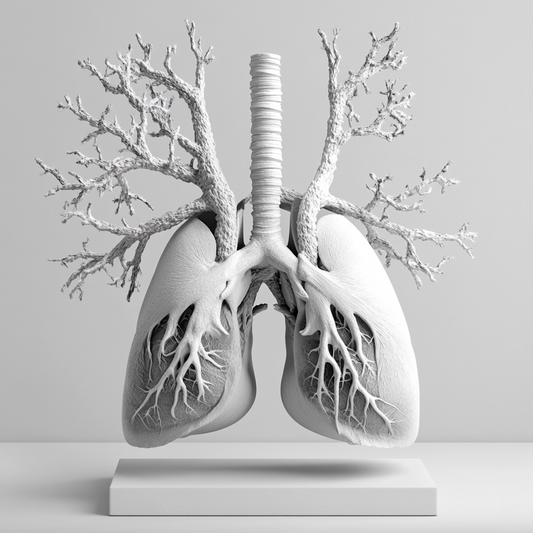

The Science of Nasal Breathing Breathing through the nose stimulates the production of nitric oxide (NO) within the paranasal sinuses. Nitric Oxide is crucial to the process of vasodilation,...

The Science of Nasal Breathing Breathing through the nose stimulates the production of nitric oxide (NO) within the paranasal sinuses. Nitric Oxide is crucial to the process of vasodilation,...